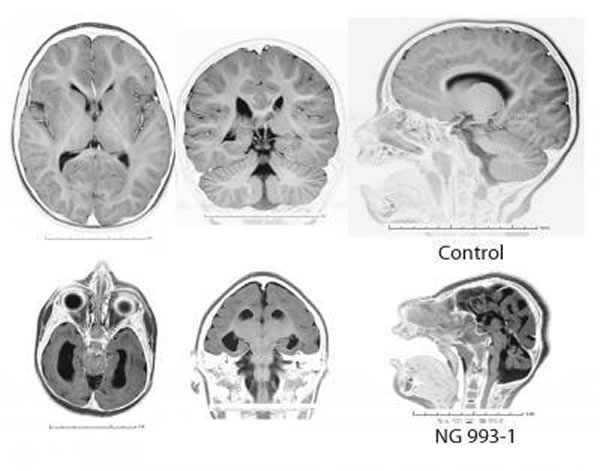

上图为正常人 下图为严重头小畸形

这项研究的研究材料来源于一个土耳其家庭和两个巴基斯坦家庭中最严重的头小畸形(microcephaly)孩子的案例。这些孩子的大脑只有正常人的十分之一,而且他们缺少正常人脑所应有的大脑皮层结构。